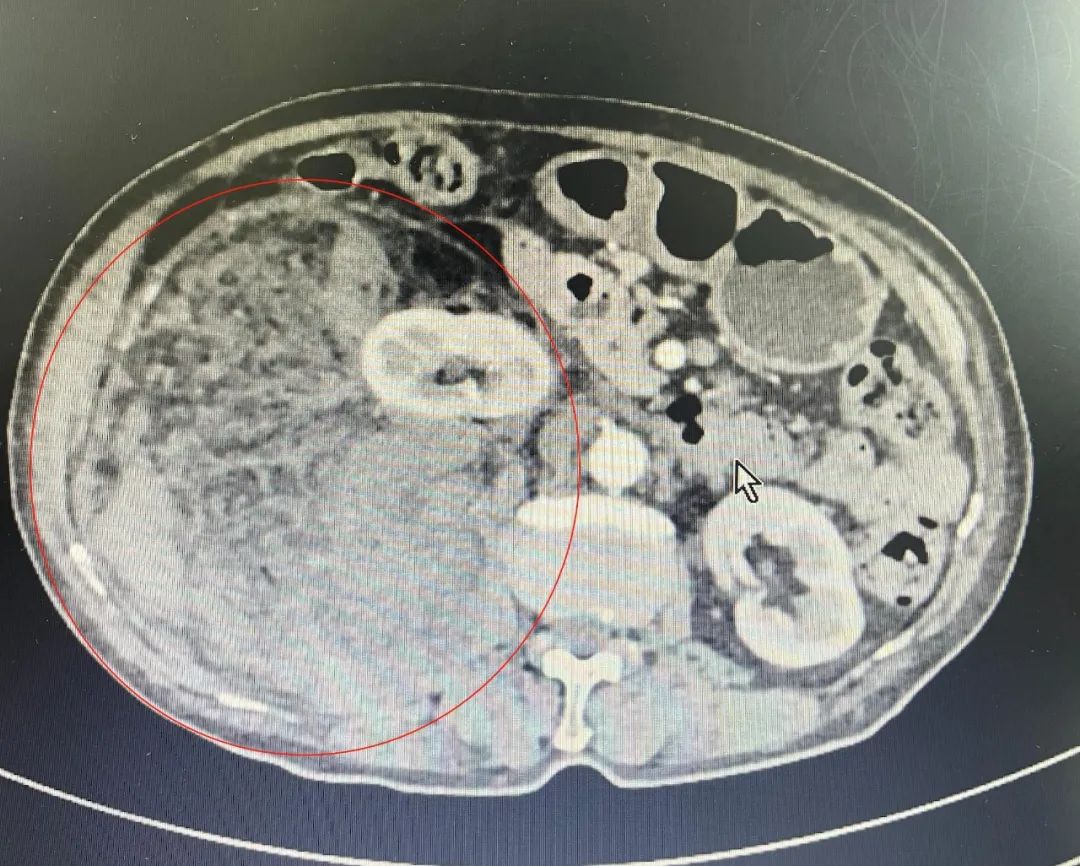

长了一颗 180 mm 的巨大肿瘤

如同一个「哈密瓜」大小

几乎占满整个右侧腹部

更令人担忧的是,在她的右侧腹部,竟能触摸到一个明显的肿物,家人也是心急如焚,立即带着洪大妈前往漳州第三医院进行检查。结果令人十分震惊,一个「哈密瓜」般大小的巨大肿物,占满了右侧腹部空间,CT 显示大小约 140 mmX87 mmX181 mm,初步考虑为「腹膜后肿瘤」。